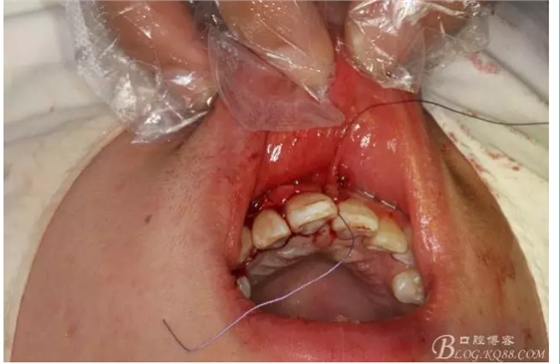

圖2.根管治療術(shù)后直接局部 麻醉下切開(kāi)、翻瓣,發(fā)現(xiàn)12唇側(cè)骨壁有綠豆大小骨缺損

圖3.依缺損部位為中心,逐漸去骨,完整暴露出囊壁。

圖4.摘除囊壁后形成的巨大骨腔

圖5.清理骨腔,可以看到12的根尖暴露在骨腔內(nèi)。